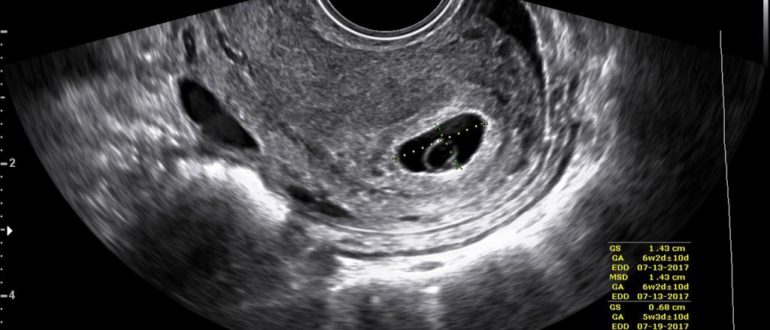

Тест положительный, а УЗИ беременности не показывает: что делать? тест положительный а узи беременность не показывает Первым анализом, который помогает определить наличие беременности, является исследование крови и мочи…

УЗИ не показало беременность

На УЗИ не увидели беременность. Так бывает? Очень волнительный момент – наступление ожидаемой беременности. Три дня задержки, две полоски на тесте, купленном в ближайшем супермаркете, и женщина уже…